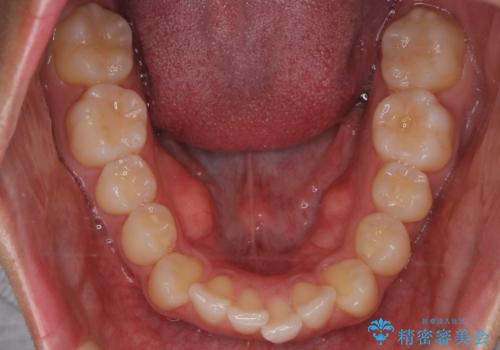

患者様よりシュミレーション通りに歯が動くか心配との事だったので

出来るだけ計画通りに歯を動かすために、マウスピース1枚あたりの使用時間を長めに使っていただきました。

そのため、多少治療期間が延びましたが、リファイメント(マウスピースの再発注)なしで終了することができました。